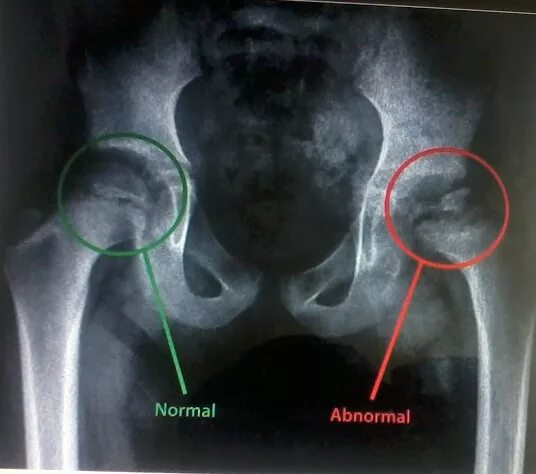

Асептический некроз инвалидность